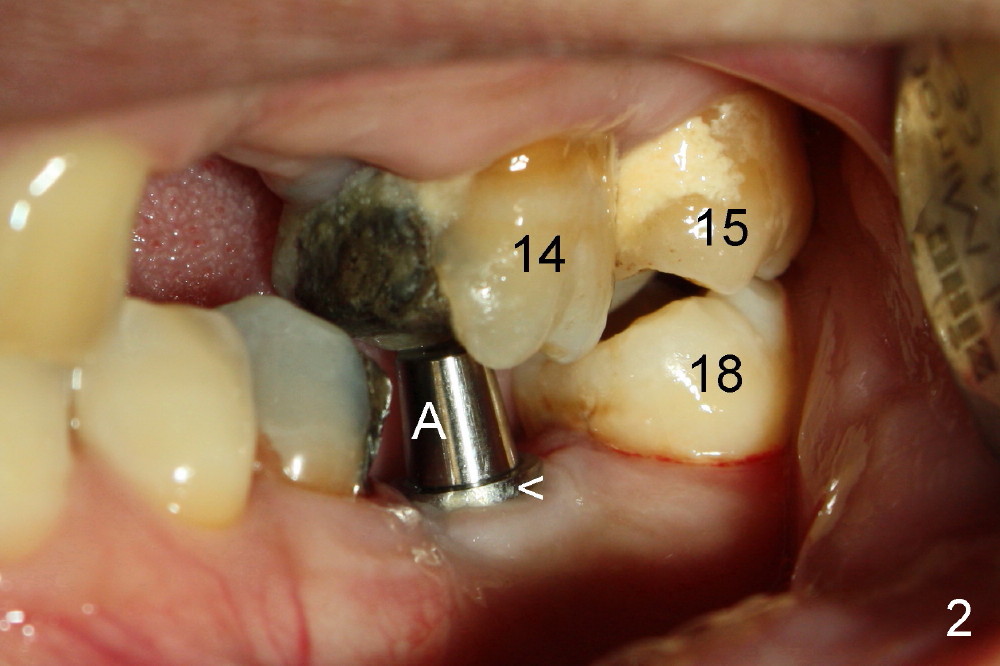

A 51-year-old man needs implants at the sites of #12,13,19 (Fig.1). The teeth #12 and 13 are extracted. An implant is placed at #19 (Fig.2 <). After osteointegration, an abutment is placed (Fig.2 A). The opposing tooth, #14, is found supraerupted. Two mini-implants are placed at the mesiobuccal and distolingual areas of #14 (Fig.3 (mirror view) <) and a power chain (*) is placed for intrusion. In the next 8 months, these 2 mini-implants become loose. Two new mini-implants are placed in the mesiolingual and distobuccal regions (Fig.4 ^). The one in the distobuccal region is loose after a while (Fig.6,7 >). In brief, mini-implants are not efficient in intrusion. At this time, the implants at the sites of #12,13 apparently osteointegrate (3 months post placement) and abutments are placed (Fig.4). Provisional crowns are fabricated (Fig.5). Brackets are placed between #11 and 15 with the bracket at #14 placed more coronally than those of the neighboring teeth (Fig.6-8). Mesially there are two excellent anchorages (#12,13) as well as the mesiolingual mini-implant. The distal anchorage is #15. In the next 5.5 months, the tooth #14 is intruded (Fig.9,10), but the 2nd molar is mobile (not as strong as #14). A longer mini-implant is placed in the distobuccal corner (>, more apical than before (Fig.7)). The distobuccal mini-implant is found to be mobile in 3 weeks (Fig.11). It appears that there is enough clearance for restoration of #19 (Fig.12). Power chains are placed between the mesiolingual mini-implant and #14 buccal tube until the appointment for crown prep. In this way, the lingual cusps may ascend (Fig.13 red arrow), while the buccal ones may descend (black arrow). The occlusal clearance will be more favorable.